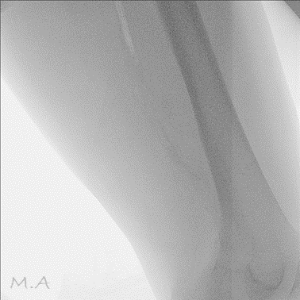

骨密度検査

骨密度検査とは、骨の中にあるカルシウムなどのミネラル量を測定し、骨粗鬆症や骨折のリスクを診断するための検査です。検査では、骨折リスクの高い部位とされる腰椎や大腿骨頚部を主に測定し、概ね5~10分程度の短時間で行うことができます。また、検査データを蓄積できるので、定期的に検査を行うことで前回との比較や年齢に応じた変化や、骨粗鬆症の早期発見と予防、治療効果の確認に役立てる事ができます。

当院では、HOLOGIC社製Horizon Wiを使用し、2種類の異なるエネルギーX線を使用するDXA法(二重エネルギーX線吸収測定法:Dual-energy X-ray Absorptiometry)による高精度な測定を行い、骨強度の指標であるTBS(骨質評価:Trabecular Bone Score)も算出可能となっています。